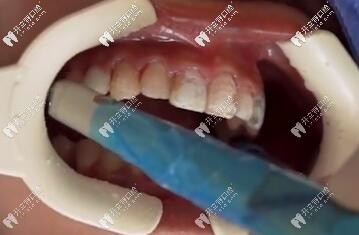

車針卸除貼面

貼面卸除

傳統(tǒng)磨除法

這種方法比較暴力,卸除離不開高速手機(jī)和車針,也是比較常用的方法,時(shí)間長,而且震動(dòng)大。